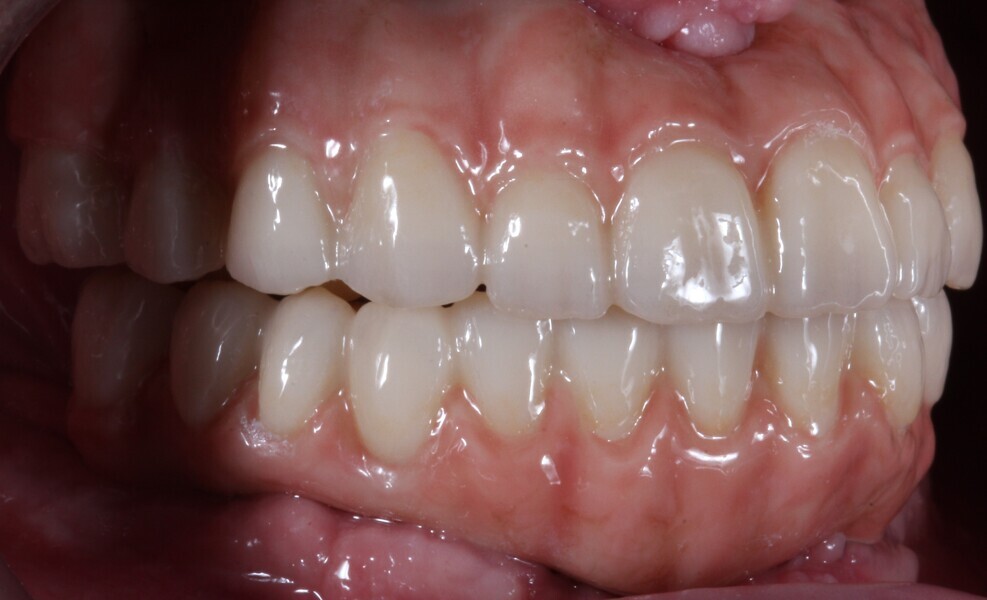

Fig. 17: The nal prosthesis on the day of delivery.

Fig. 18: Final prostheses of monolithic KATANA Zirconia YML, stained using CERABIEN ZR FC Paste Stain. The dark gingiva spots were stained with the shade Red, the light pink surfaces with the shade Pink and the highlights with the shade Salmon Pink.

Fig. 19: Final prostheses, right side view. The cervical parts were stained with the shade Cervical 2, the incisal two thirds of the anterior teeth with the shade Grayish Blue and the mamelons with the shade Mamelon Orange 1.

Fig. 20: Final prostheses, left side view.